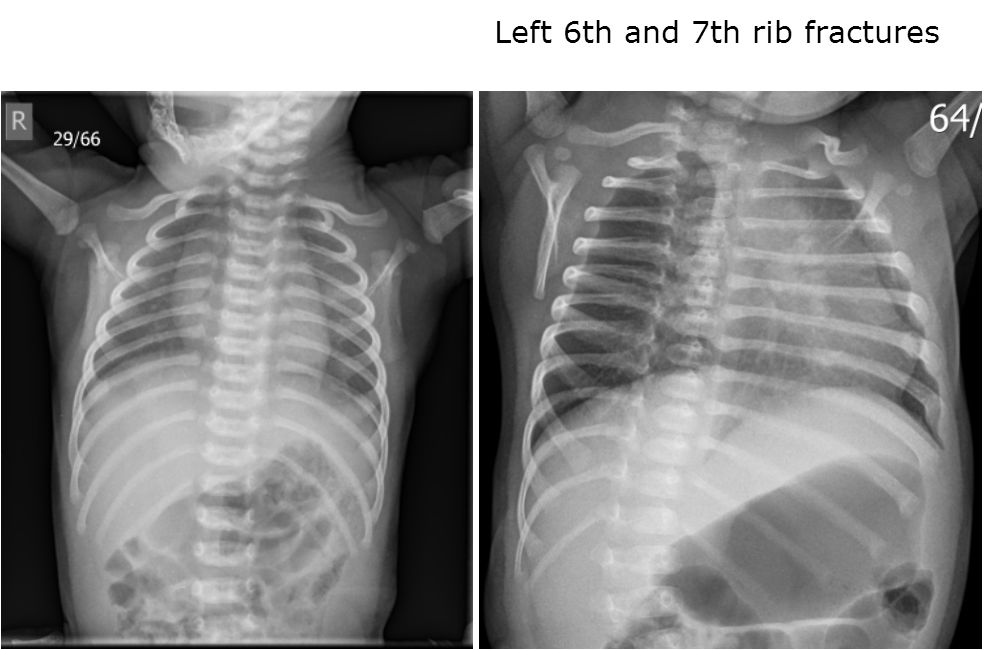

Expert – Follow up X-rays Show Makenzie Sustained Rib Fractures in the State’s Care

A follow-up skeletal survey 13 days later on November 6, 2014, showed a new healing rib fracture of the lateral left 6th rib and possible 7th lateral rib fracture. The CML was completely healed.

These rib fractures occurred while Makenzie was in South Carolina foster care.

Chest x-ray from 10/24/2015 Chest x-ray from 11/6/2015

Makenzie Walls’ x-rays from Greenville Memorial Hospital (GMH).